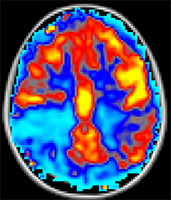

Arterial Spin Labeling

Matlab-based arterial spin labeling (ASL) software developed by Dr. Manus Donahue (Vanderbilt University Medical Center). The ASL software toolkit is designed to process Philips PAR/REC and DICOM ASL images and includes functionality for motion correction, labeling efficiency correction, T1-correction for hematocrit, slice time correction, surround subtraction, and utilizes the simplified ISMRM Perfusion Study Group kinetic model for cerebral blood flow (CBF) determination. Motion correction requires FSL installation.

Vandpire ASL Toolbox

Vandpire ASL Toolbox: A Novel Data-processing Pipeline for Imaging Research (VANDPIRE) developed by Dr. Daniel Arteaga and Manus Donahue (Vanderbilt University Medical Center). VANDPIRE is an intuitive and comprehensive software for quantifying cerebral blood flow (CBF) and calculating CBF territories based upon arterial spin labeling (ASL) MRI data. CBF analysis, particularly CBF territory analysis, is time-consuming and requires an advanced knowledge of scripting and up-to-date mathematical models. As a result, many researchers who are interested in performing such analyses are unable to do so. This toolbox addresses these concerns, and additionally is available on multiple platforms as a graphical user interface, making such analyses much more accessible to researchers. Academic users may license and download the VANDPIRE software free of charge.